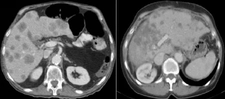

Tanı YöntemleriKafa içindeki lezyonların tanısı, genellikle hem klinik muayene hem de görüntüleme yöntemleri ile konulur. Kullanılan başlıca yöntemler şunlardır: